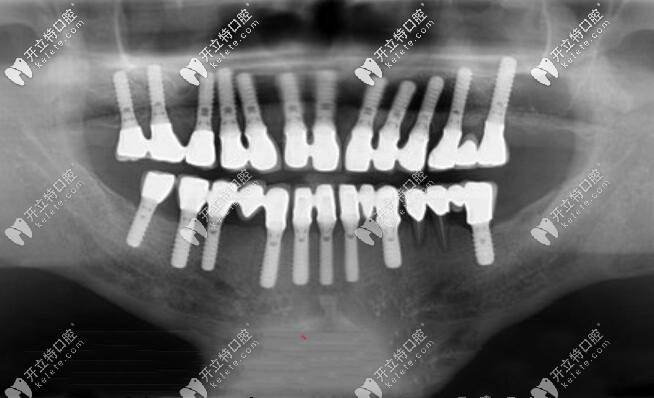

傳統(tǒng)的全口種植牙X光片▼

傳統(tǒng)的全口種植牙X光片